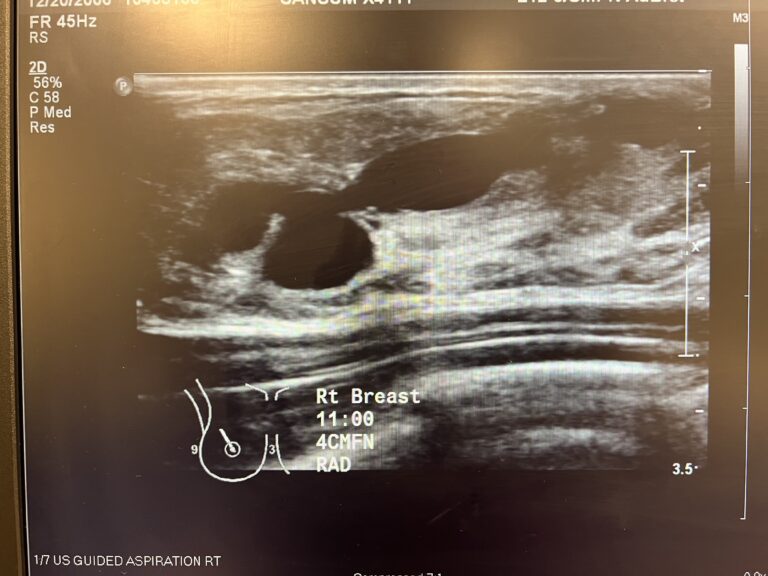

Ultrasound appearance of sebaceous cyst with tract to skin.